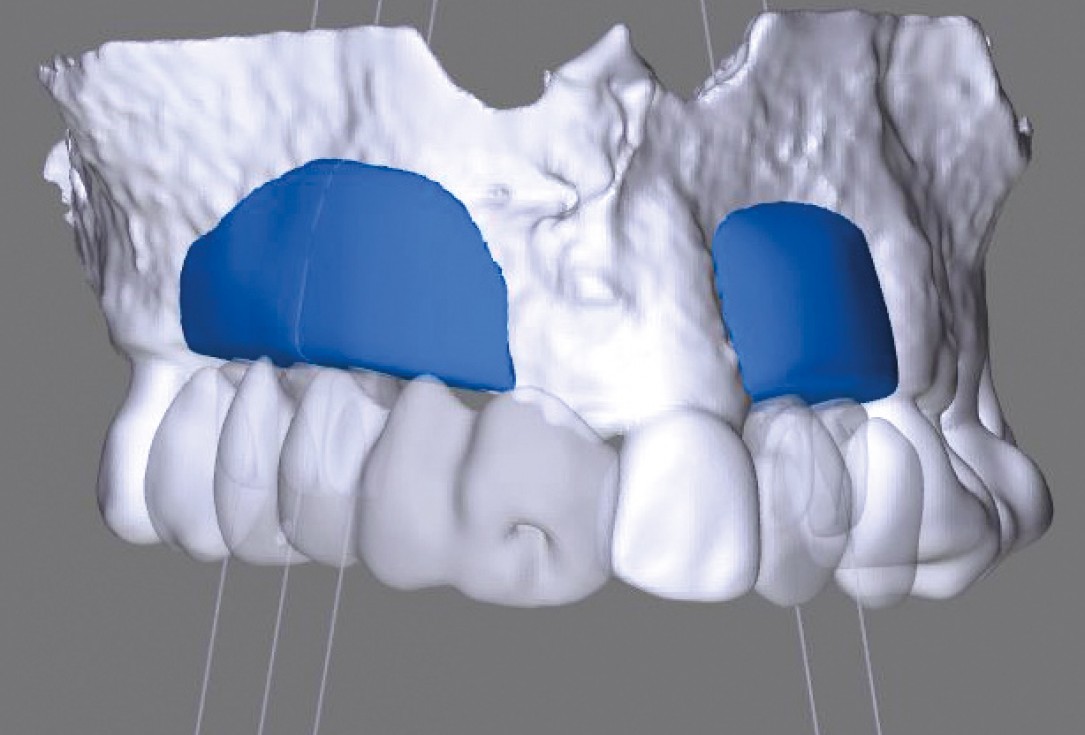

Initial situation: X-ray scan reveals eggshell thin sinus floor (1-3 mm) on both sites of the maxilla; green areas indicate the planned maxgraft® bonerings and red areas the planned implants